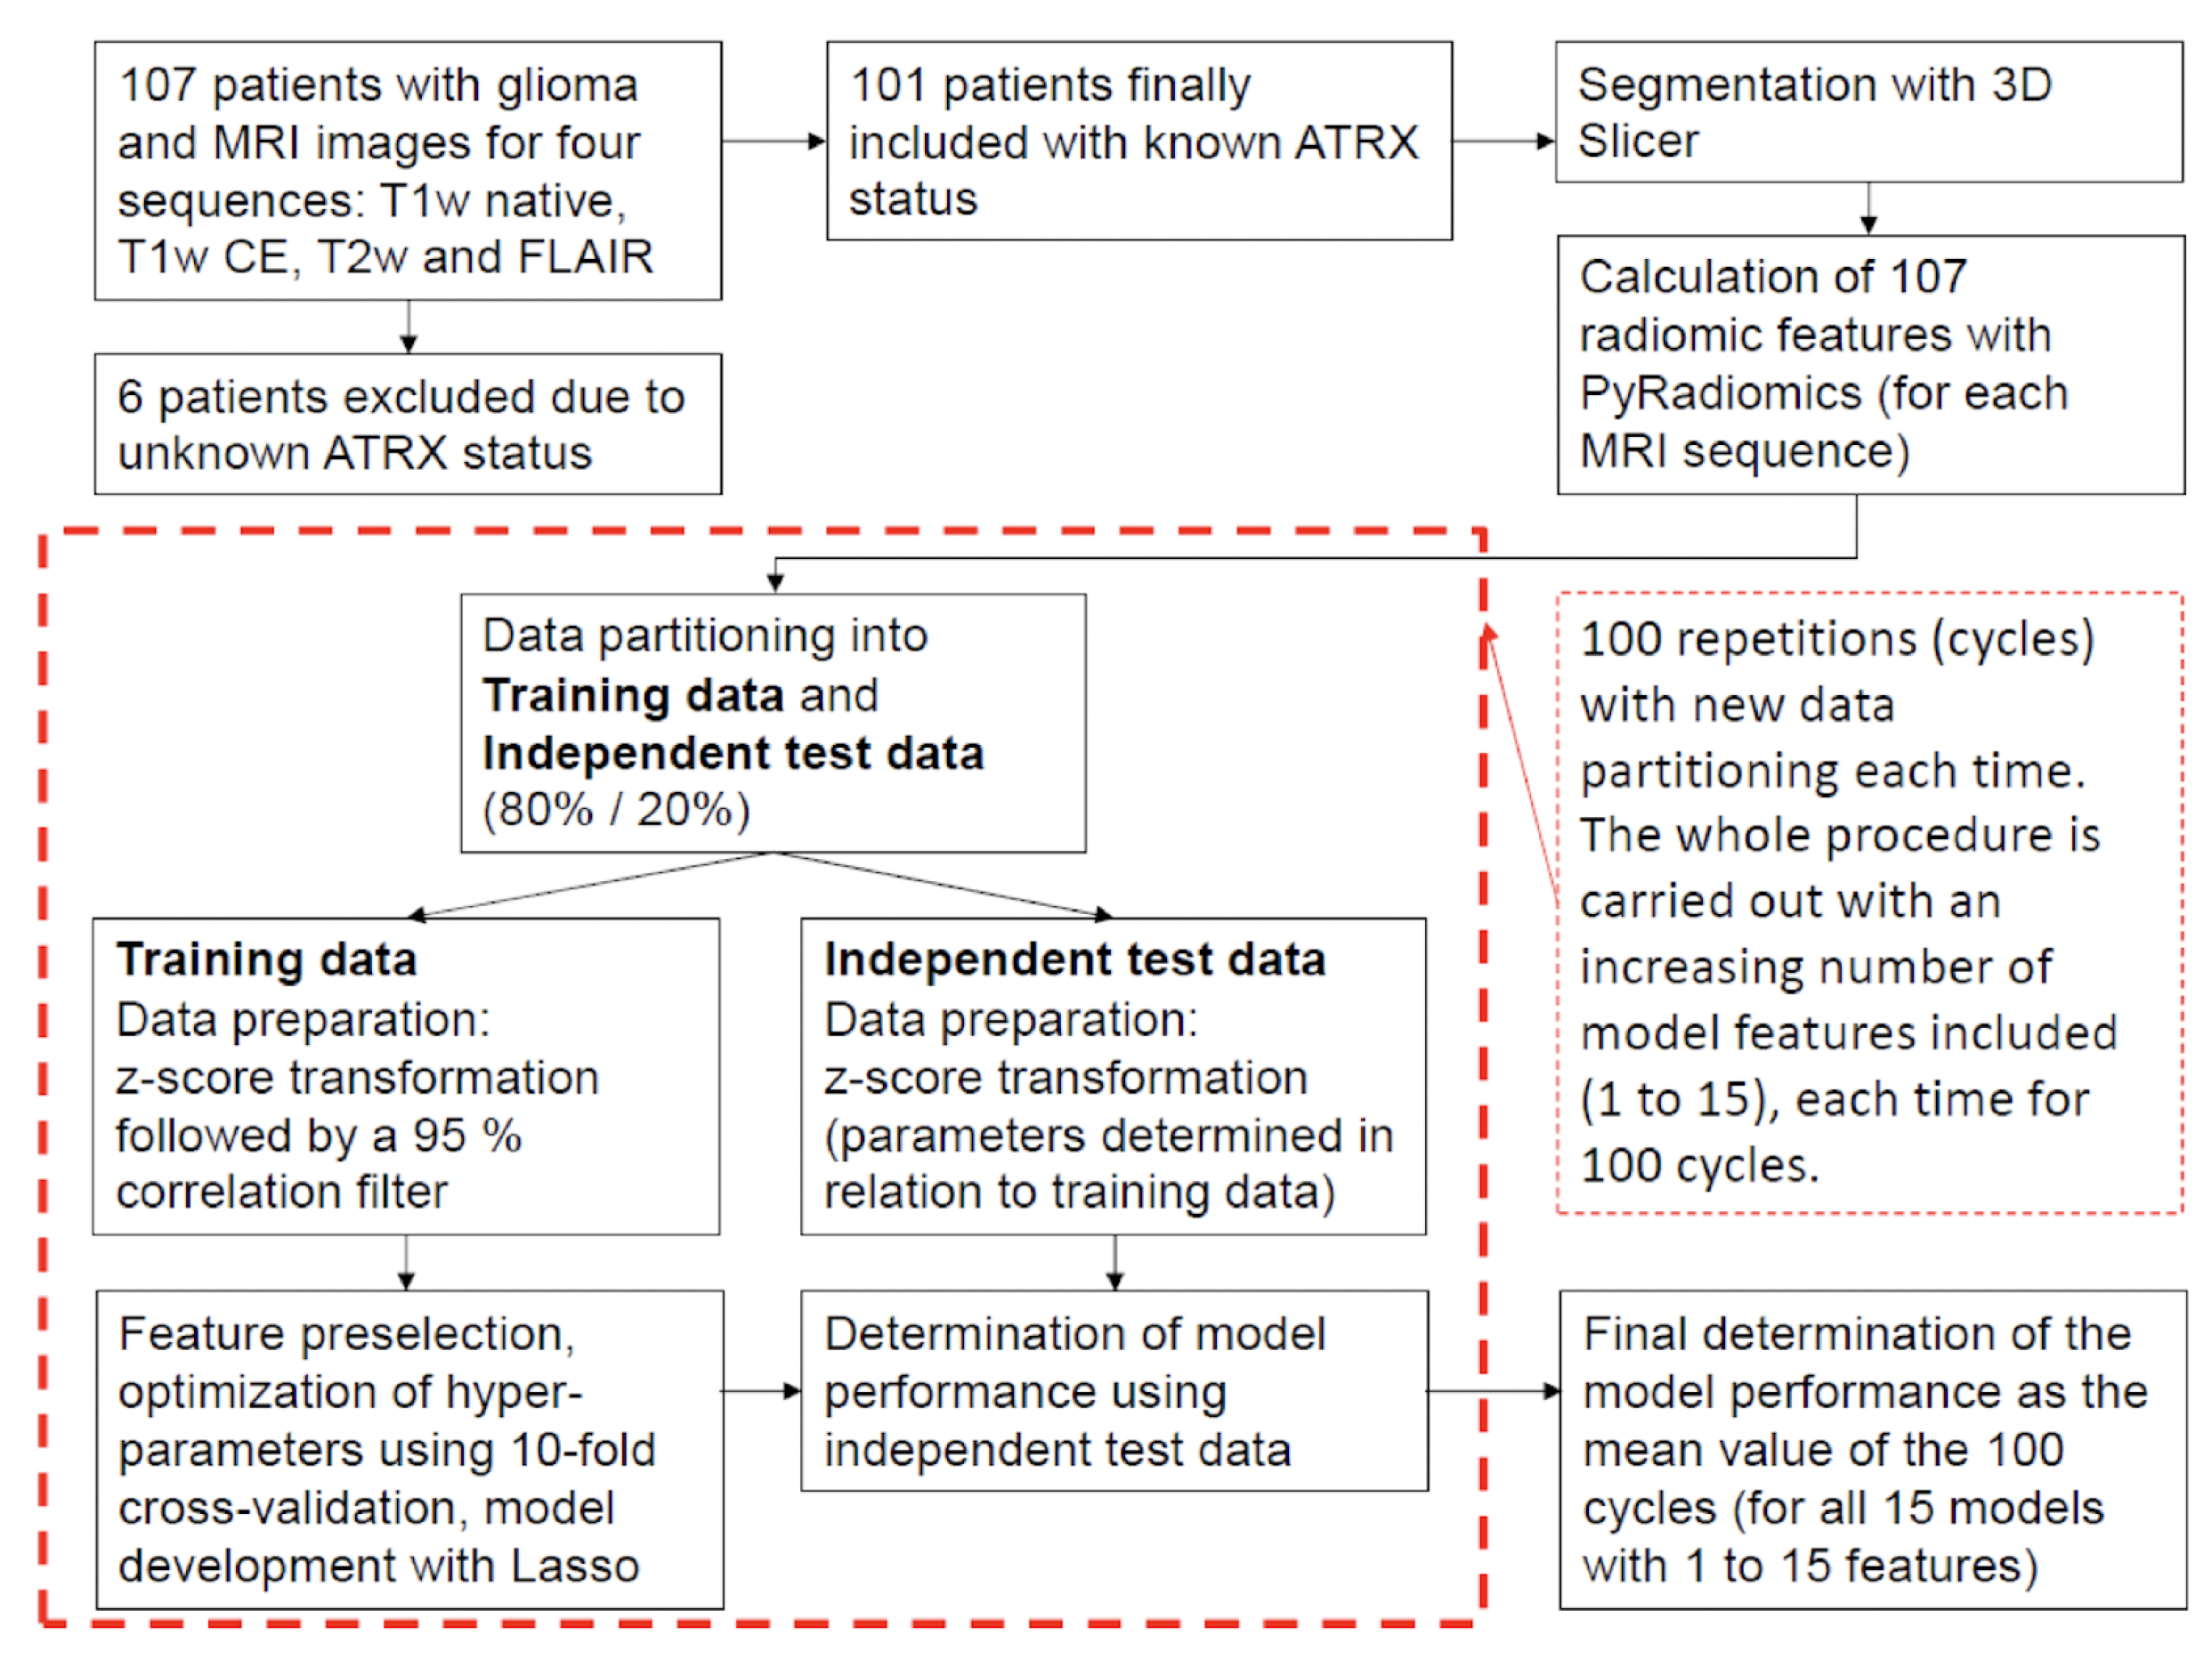

2. Materials and Methods

2.1. Radiomics

2.2. Statistical Analysis